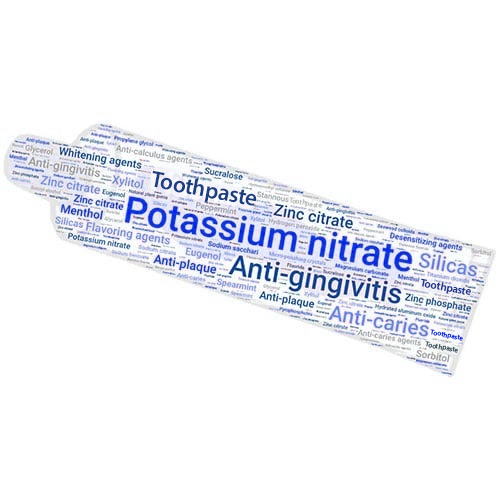

Introducción a la crema dental

¿Conoce la importancia de la crema dental para una buena salud bucal, pero no sabe qué ingredientes contiene exactamente y por qué? ¡Le damos la bienvenida a una introducción sobre las cremas dentales!